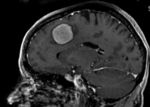

Slicer Registration Library Case #1: Follow-up MRI of Brain Tumor

This case contains a baseline-followup pair of brain MRI. Goal is to align the follow-up image with the reference/baseline scan to assess changes, particularly in the tumor region.

Approach: Since image contrast and content is very similar in both images, and there is a good amount of initial overlap, the standard Slicer automated registration should work well for this. If possible, and affine registration would be preferable to a rigid one to address the typical distortions that occur in MRI and often vary between scans. However to assure the tumor and tumor changes do not influence the result, we will build a mask that excludes the tumor region from participating (i.e. actively contributing toward the result transform). We also use this case as an example to illustrate how to quickly generate masks for registration.

MRI, brain, head, intra-subject, meningioma